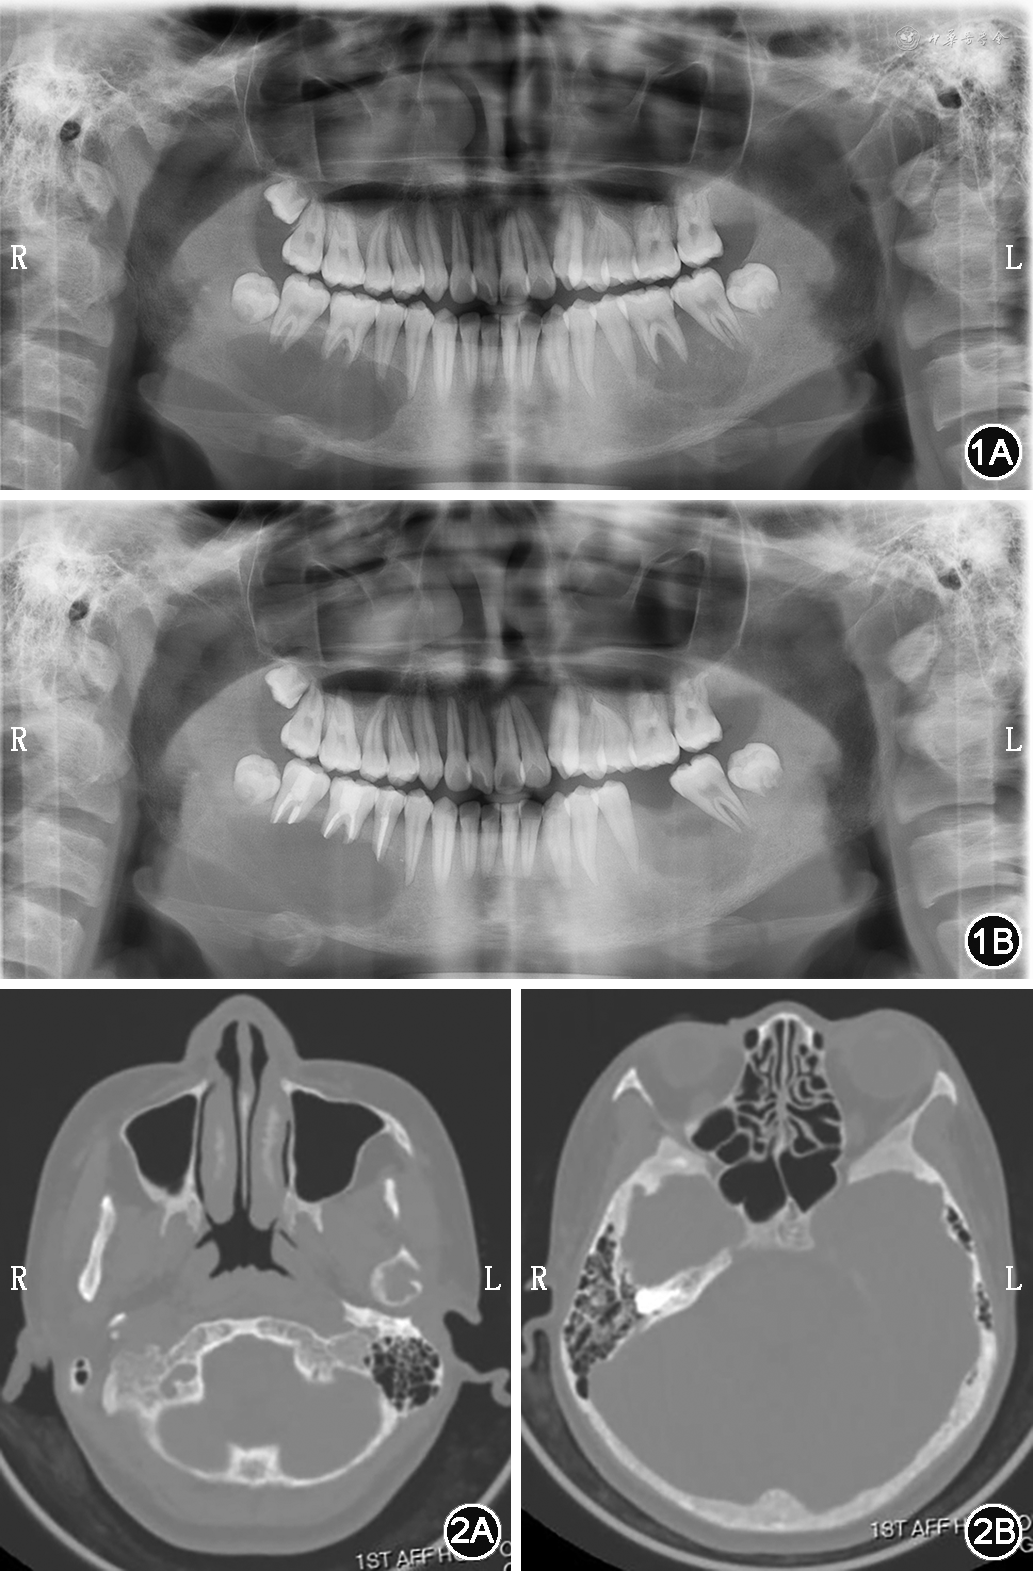

患者女,21岁,以“面部不对称半年余”为主诉于2019年2月10日就诊于蚌埠医学院第一附属医院口腔颌面外科。患者既往健康状况良好,无手术等特殊病史。专科检查示:颜面部不对称,右侧下颌角区可触及约3 cm×4 cm范围骨质膨隆,边界尚可,无压痛;左侧颞下颌关节区较右侧稍膨隆,无压痛;双侧颞下颌关节活动对称,开闭口运动时关节无弹响、压痛;下唇无麻木感,双侧颈部、颌下及颏下淋巴结未触及肿大;张口度3.6 cm,张口型正常。口腔内未见明显异常。曲面断层片显示:右髁状突及左、右下颌骨体部可见单房椭圆形囊状破坏区,边缘无切迹,透光区不明显(图1)。入院后行颌骨CT平扫时发现,双侧下颌骨体部、升支、髁状突、枕骨、蝶骨弥漫性骨质密度海绵质样增高伴多发骨质破坏(图2)。生化常规:总钙离子2.46 mmol/L,离子钙1.32 mmol/L,无机磷0.78 mmol/L。完善相关检查后,拟行下颌骨病变刮治术。术中右髁状突采用耳屏前切口,其他均采用口内下颌颊侧前庭沟切口。术中见病灶区骨质菲薄,内含巨大创腔,无明显分隔,内容物见大量息肉样物质,刮出部分内容物送冰冻检查,结果示梭形细胞增生性病变,倾向良性。而后彻底刮除肿物,并用稀碘液浸泡创腔。术后给予抗感染、消肿、止痛等对症治疗。术后1周出院,伤口一期愈合。病理示病变主要由增生的纤维结缔组织背景中散在多核巨细胞构成(图3A、3B)。间质为梭形纤维母细胞样细胞,并有成为结节的趋势。病灶内常有出血,周围可有骨样组织及骨小梁再生。破骨细胞样多核巨细胞多在新生骨周围或围绕出血区域分布(图3C)。两侧送检组织镜下图像一致。术后患者面型较前无明显变化,按照术后1、3、6、12个月随访,共随访12个月,术后12个月颌面部曲面断层片显示下颌骨病灶区较之前有新生骨质形成。